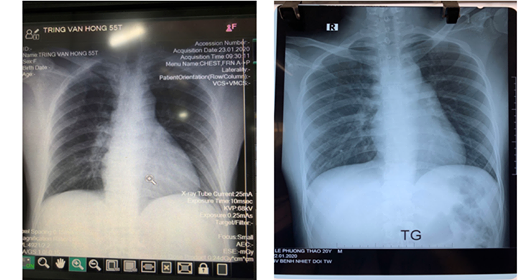

| Tại buổi làm việc, Bệnh viện Bệnh Nhiệt đới Trung ương cơ sở 2 đã báo cáo 2 trường hợp nghi ngờ mắc viêm phổi cấp do chủng nCoV mới. Trường hợp đầu tiên là bệnh nhân nữ LPT (20 tuổi, P. Phú Lãm, Q. Hà Đông, Hà Nội) là sinh viên đi du học tại thành phố Vũ Hán, tỉnh Hồ Bắc, Trung Quốc. Bệnh nhân được chẩn đoán bị sốt (chưa loại trừ nhiễm Coronavirus). Trước đó, bệnh nhân này sống ở khu vực được Chính phủ Trung Quốc thông báo trong vùng an toàn, không tiếp xúc với người có biểu hiện ho, sốt hoặc nghi mắc viêm phổi do nCoV trong vòng 2 tuần trước khi về nước. Bệnh nhân về nước 8 ngày, không tiếp xúc với người bị ốm, sốt. Hiện, bệnh nhân đang được điều trị tại khu cách ly.

Trường hợp thứ 2 là nam bệnh nhân TVH (55 tuổi, Lý Thường Kiệt, H. Yên Mỹ, Hưng Yên) cũng được chẩn đoán bị sốt (chưa loại trừ nhiễm Coronavirus). Bệnh nhân đang được điều trị tại khu cách ly trong tình trạng khó thở, tiếp tục được theo dõi, giám sát. Hiện, Bệnh viện Bệnh Nhiệt đới Trung ương cơ sở 2 có 3/6 phòng cách ly áp lực âm (của cả nước); 100 giường bệnh để sẵn sàng tiếp nhận và theo dõi bệnh nhân. Bệnh viện cũng có đội cấp cứu lưu động sẵn sàng hỗ trợ cho địa phương. Để sẵn sàng ứng phó với dịch bệnh, bệnh viện đã đề nghị xin thêm 20 máy thở, 4 máy X-quang tại giường; trang phục phòng hộ. Bệnh viện cũng đã gửi công văn cho các sở y tế các tỉnh để chuyển bệnh nhân về cơ sở 2 Kim Chung, Đông Anh, Hà Nội. |